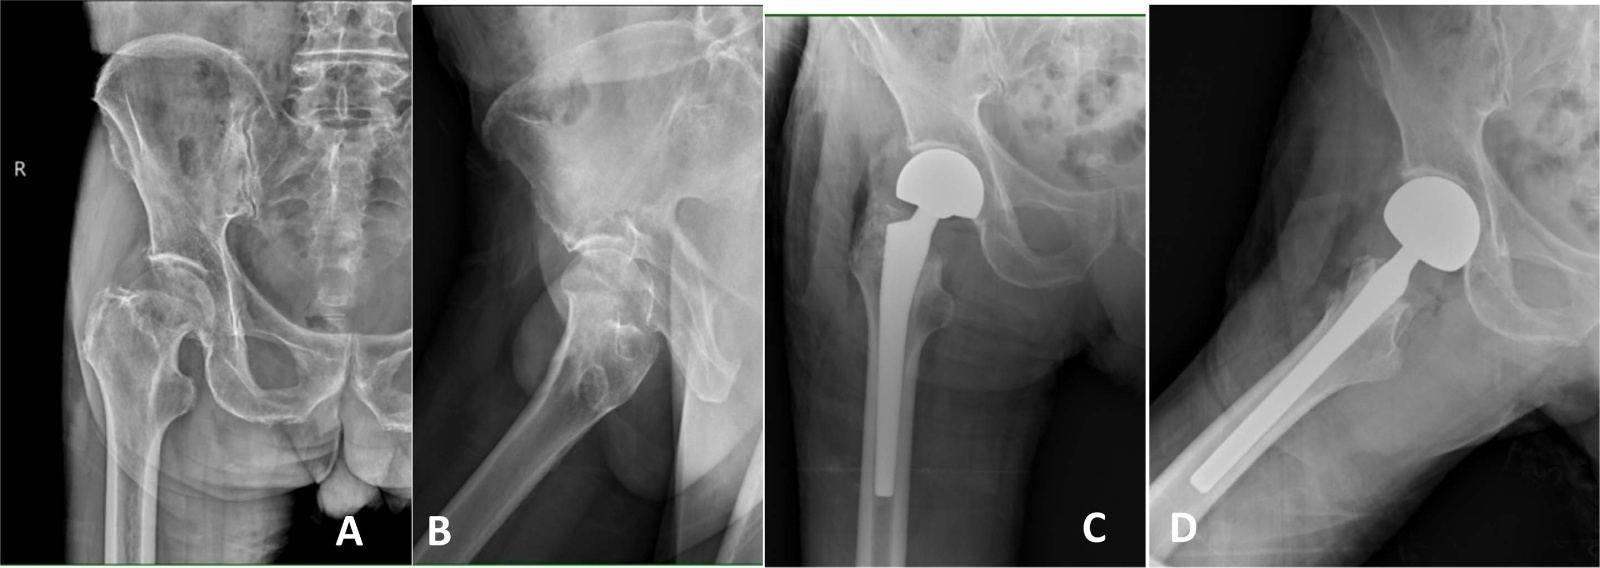

典型病例影像学表现见图1~5图1为76岁女性右侧股骨颈骨折(Garden Ⅲ型)患者,DAA入路半髋关节置换术前X线示骨折断端部分错位,术后X线示假体位置良好,股骨近端微裂予钢丝捆扎固定;图2为83岁女性左侧股骨颈骨折(Garden Ⅳ型)患者,术后X线示假体位置良好;图3为75岁男性右侧股骨颈骨折(Garden Ⅱ型)患者,术后假体位置满意;图4为73岁女性左侧股骨颈骨折(Garden Ⅲ型)患者,术后假体匹配良好;图5为80岁男性右侧股骨颈骨折(Garden Ⅱ型)患者,术后假体位置正常。

Figure 1. X-ray films before and after surgery of a 76-year-old female patient with right femoral neck fracture (Garden type III) A, B: Before surgery; C, D: After surgery

1. 76岁女性右侧股骨颈骨折(Garden Ⅲ型)患者手术前后X线片A、B:术前;C、D:术后